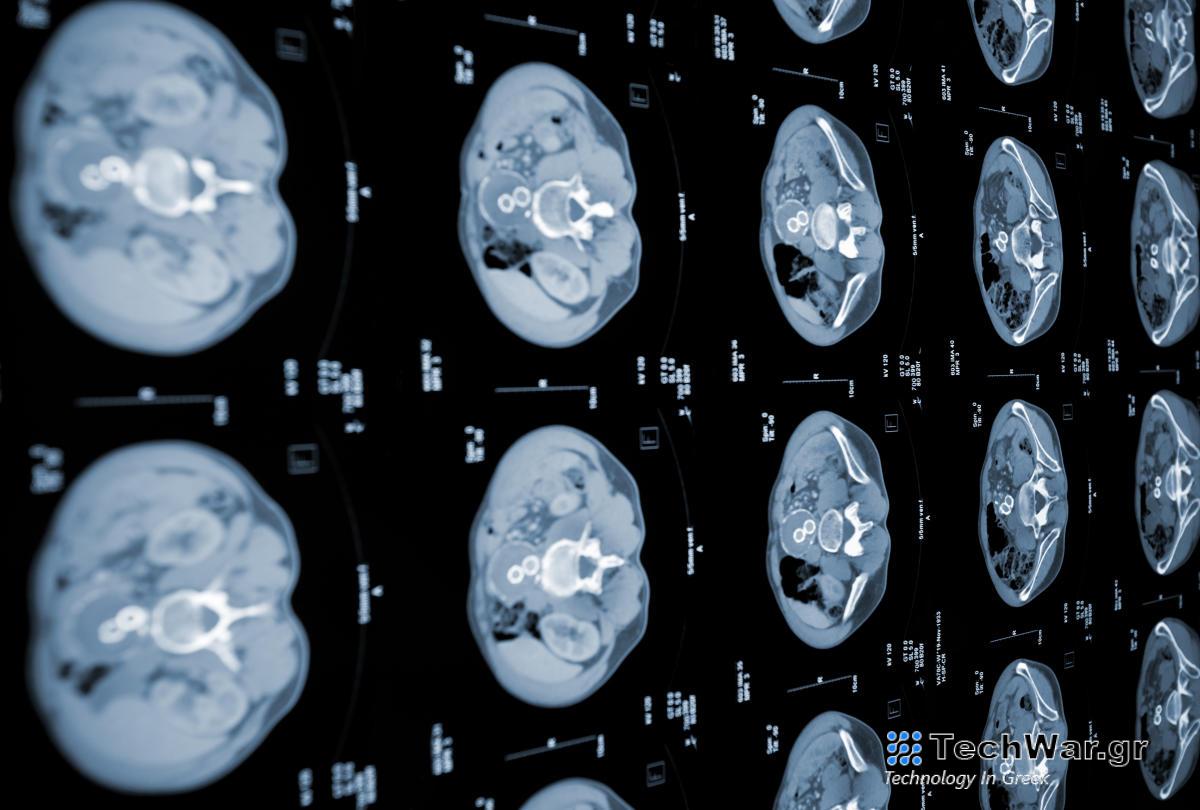

ούργησε δύο αλγόριθμους μηχανικής μάθησης που μπορούν να ανιχνεύσουν τον καρκίνο του παγκρέατος σε υψηλότερο όριο από τα τρέχοντα διαγνωστικά πρότυπα. Τα δύο μοντέλα μαζί σχηματίστηκαν για να δημιουργήσουν το νευρωνικό δίκτυο «PRISM». Έχει σχεδιαστεί για να ανιχνεύει ειδικά το αδενοκαρκίνωμα του παγκρεατικού πόρου (PDAC), την πιο διαδεδομένη μορφή καρκίνου του παγκρέατος.

Τα τρέχοντα τυπικά κριτήρια προσυμπτωματικού ελέγχου PDAC πιάνουν περίπου το 10 τοις εκατό των περιπτώσεων σε ασθενείς που εξετάζονται από επαγγελματίες. Συγκριτικά, το PRISM του MIT ήταν σε θέση να αναγνωρίσει περιπτώσεις PDAC στο 35 τοις εκατό του χρόνου.

Αν και η χρήση δεν είναι ένα εντελώς νέο επίτευγμα, το PRISM του MIT ξεχωρίζει λόγω του τρόπου με τον οποίο αναπτύχθηκε. Το νευρωνικό δίκτυο προγραμματίστηκε με βάση την πρόσβαση σε διάφορα σύνολα πραγματικών ηλεκτρονικών αρχείων υγείας από ιδρύματα υγείας σε όλες τις ΗΠΑ. Τροφοδοτήθηκε με δεδομένα από περισσότερα από 5 εκατομμύρια ηλεκτρονικά αρχεία υγείας ασθενών, τα οποία οι ερευνητές από την ομάδα είπαν ότι «ξεπέρασαν την κλίμακα» των πληροφοριών που τροφοδοτήθηκαν σε ένα μοντέλο τεχνητής νοημοσύνης σε αυτόν τον συγκεκριμένο τομέα έρευνας. “Το μοντέλο χρησιμοποιεί κλινικά και εργαστηριακά δεδομένα ρουτίνας για να κάνει τις προβλέψεις του και η ποικιλομορφία του πληθυσμού των ΗΠΑ είναι μια σημαντική πρόοδος σε σχέση με άλλα μοντέλα PDAC, τα οποία συνήθως περιορίζονται σε συγκεκριμένες γεωγραφικές περιοχές όπως μερικά κέντρα υγειονομικής περίθαλψης στις ΗΠΑ,” Kai Jia , είπε ο ανώτερος συγγραφέας της

Το AI λειτουργεί αναλύοντας δημογραφικά στοιχεία ασθενών, προηγούμενες διαγνώσεις, τρέχοντα και προηγούμενα φάρμακα σε σχέδια φροντίδας και εργαστηριακά